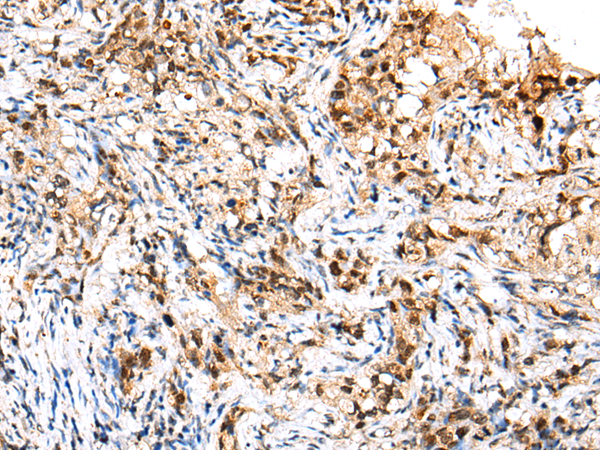

ELISA, IHC |

IHC positive control: |

Human esophagus cancer and human lung cancer |

IHC Recommend dilution: |

25-100 |